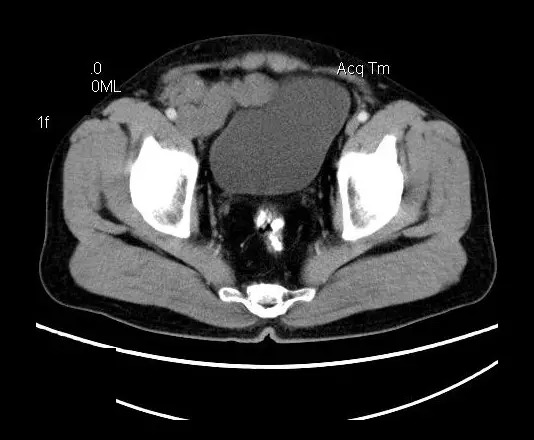

【影像表现】

盆腔右前侧及邻近腹股沟区可见多发大小不等的聚集生长的结节影,病灶呈软组织密度,边缘尚规整,分界尚清,增强扫描可见不均匀强化。膀胱局部受压,盆腔未见明显肿大淋巴结影。

“盆腔”多发性神经鞘瘤